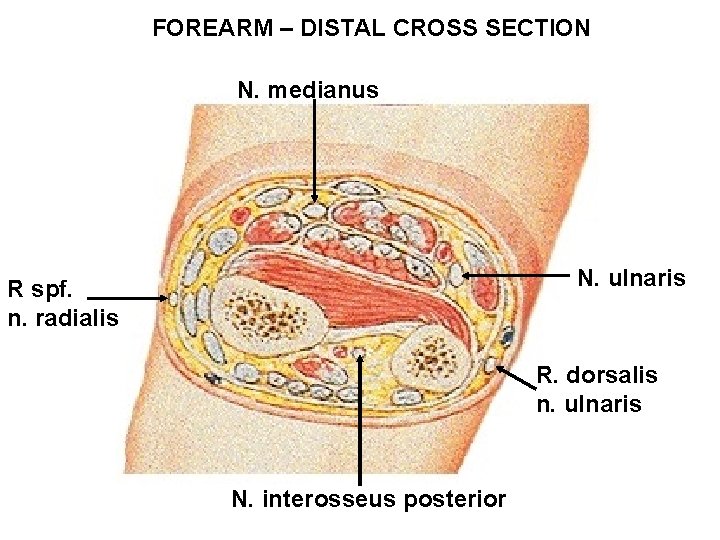

FOREARM – DISTAL CROSS SECTION N. medianus N. ulnaris R spf. n. radialis R. dorsalis n. ulnaris N. interosseus posterior